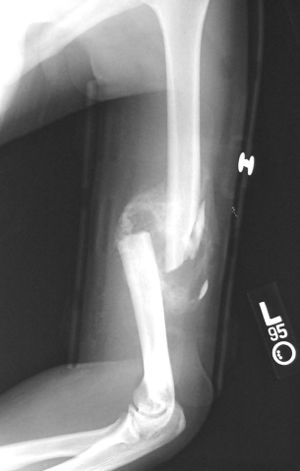

Humerus fracture

Humerus Fractures